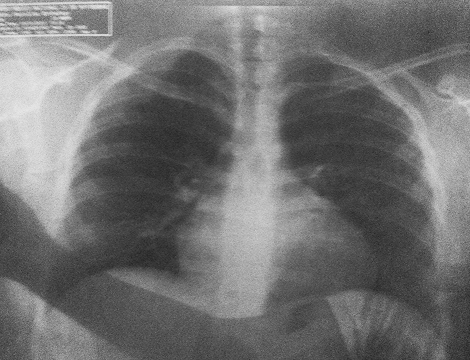

Paciente Esthefany Medina

Paciente diagnosticada con hipertrofia cardíaca (cardiomegalia), una condición caracterizada por el agrandamiento del corazón debido al engrosamiento de sus paredes musculares o la dilatación de sus cavidades.

A través del tratamiento, se buscó regular el flujo de energía y calmar el fuego interno, ayudando al corazón a recuperar su equilibrio funcional y emocional.

Evolución del corazón inflamado

2014